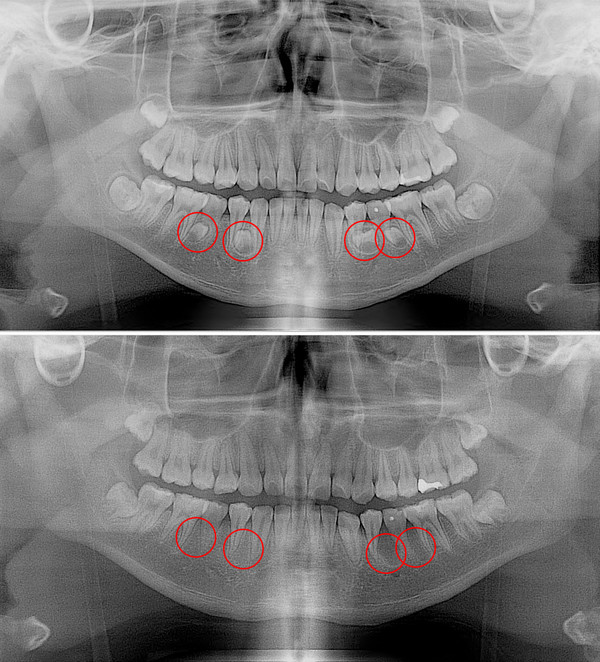

일반적으로 사람의 구강에는 28개의 영구치와 4개의 사랑니가 나와 총 32개의 치아가 자라게 되어있으나, 이보다 더 많거나, 불필요한 치아가 추가로 생기는 경우 이를 과잉치라 한다.

과잉치가 발생하는 정확한 원인은 밝혀지지 않았다. 다만 부모나 형제에게 과잉치가 있으면 발생 확률이 높아지는 것으로 보고 있다. 대부분이 턱뼈 내에 매복돼 있기 때문에 당사자 또는 보호자가 미리 알기는 매우 어렵다. 파노라마 방사선 촬영과 근단 방사선 사진 촬영, CT 촬영 등을 통해서만 발견할 수 있다.